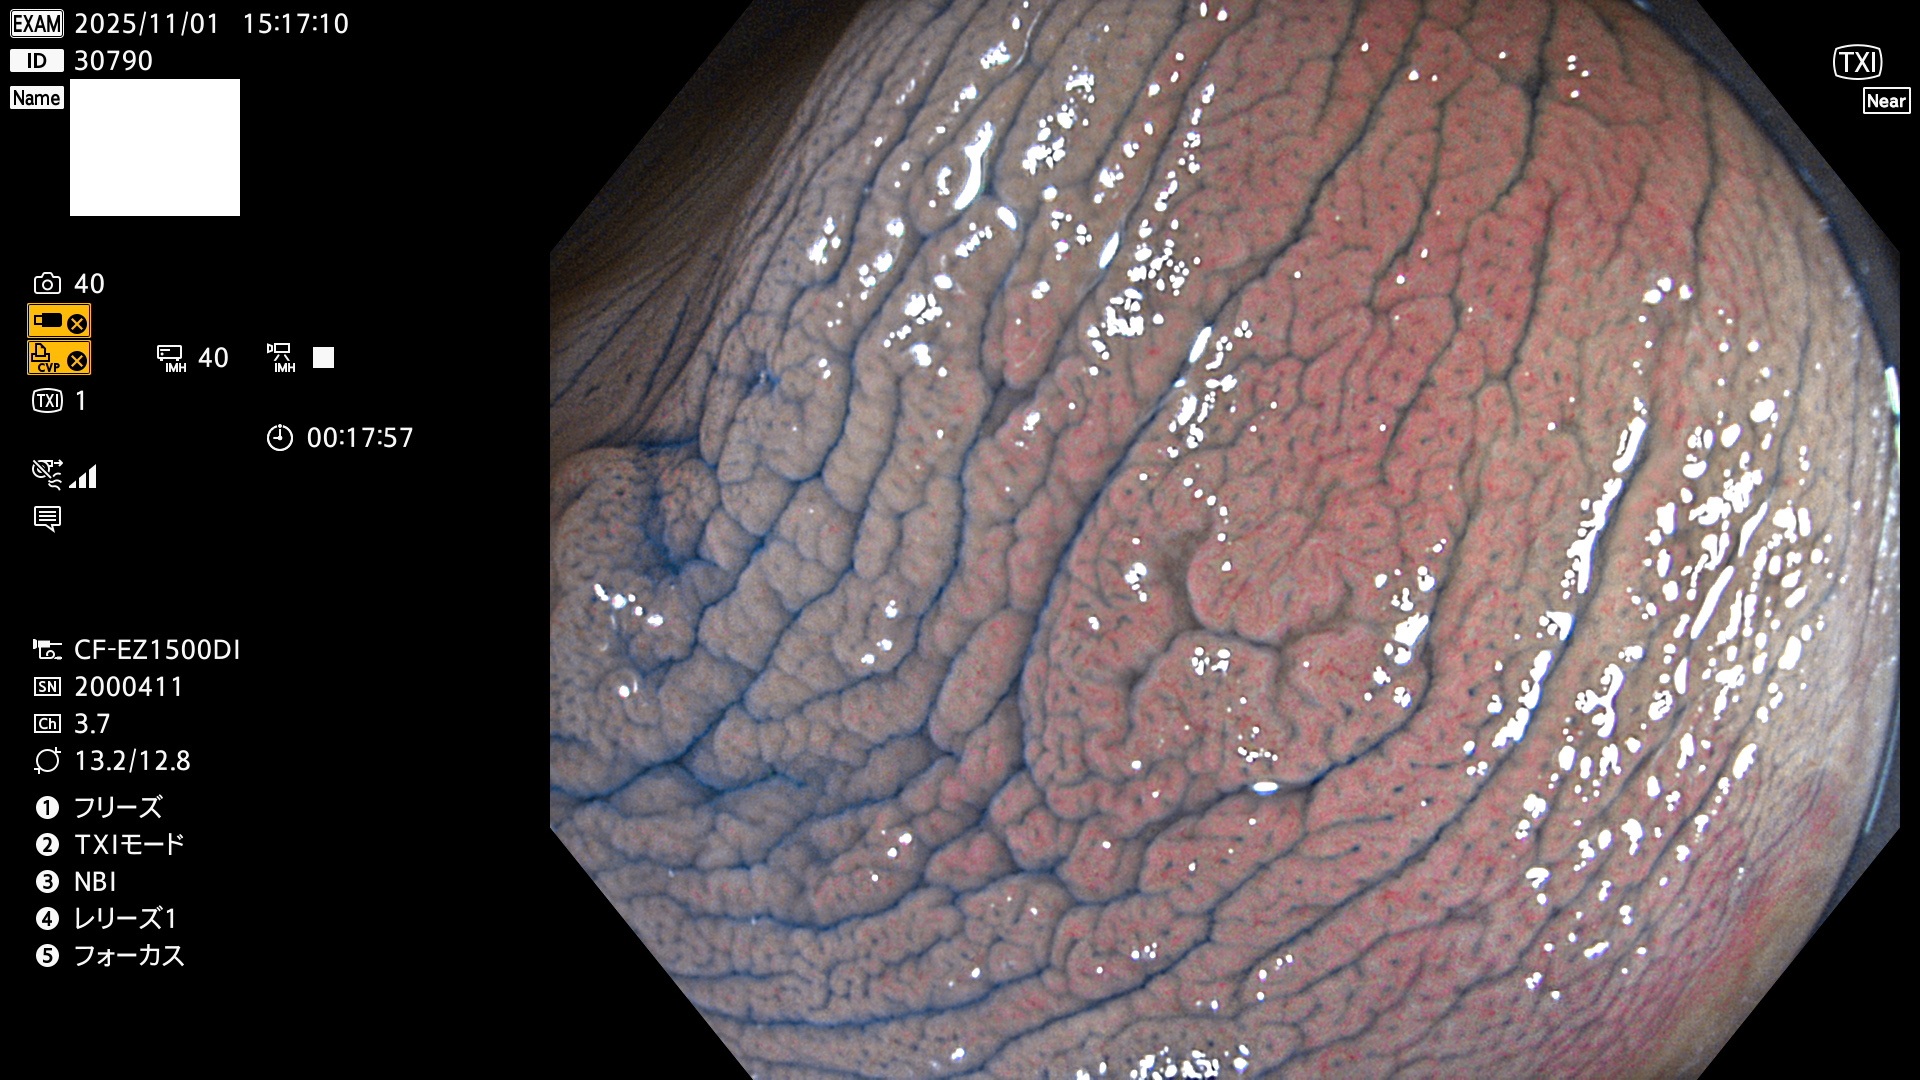

完全に平坦な物をUb、陥凹している物をUcと呼びます。Ubは認識が困難で、Ucはびらん(炎症)と紛らわしいために見落とされやすく、「内視鏡後・大腸癌」の原因になります。

毎週の検査(木・金・土・日)に発見されたUbとUc型・腺腫を、その週の日曜の夜にUPし1週間、提示します。

2025年10月30日〜11月2日の4日間(40件)9個 (Uc_ADR=9個/40人=23%)